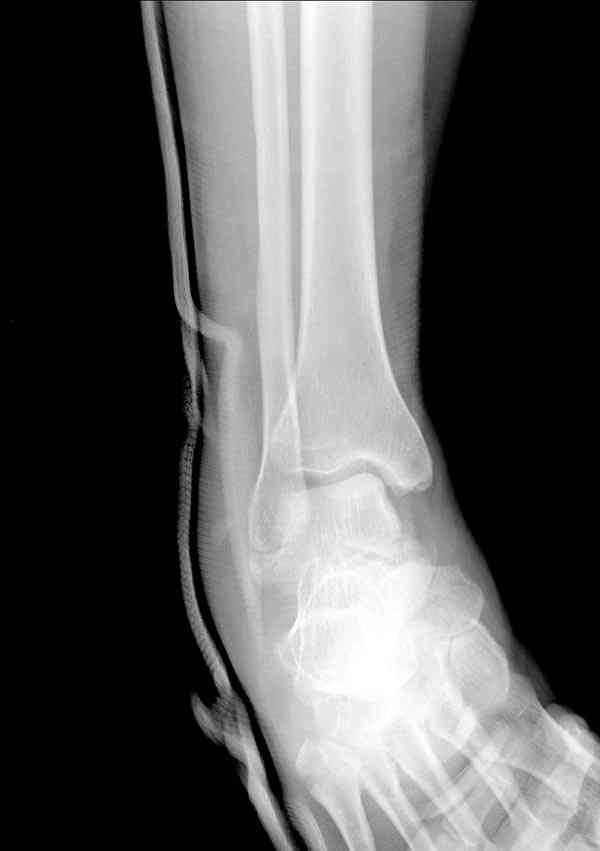

И второй случай из недавней ташкентской практики, (извините за

качество ренгенограммы и только в одной проекции) случай падения с

высоты (кстати моего друга - известного киноактера) - открытый

смещенный перелом тарана, с переломом переднего края дистального

эпиметафиза большеберцовой кости.

При поступлении в приемной сделана первичная обработка с ушиванием

открытой латеральной раны и вытяжением за пятку.

Из-за отсутствия времени пришлось оперировать на второе утро, из

материала, что имеем на месте, фиксирован двумя шурупами, а третий-это

контур сломанного жойстика в 4 мм. На дистальный медиальный конец

тибиа antiglide 3.5 мм пластина. Через пару дней выписан и несмотря на

предупреждение, самостоятельно начал нагрузку в 4 недели, время не

ждет, снимается в боевике в Росийской Федерации.